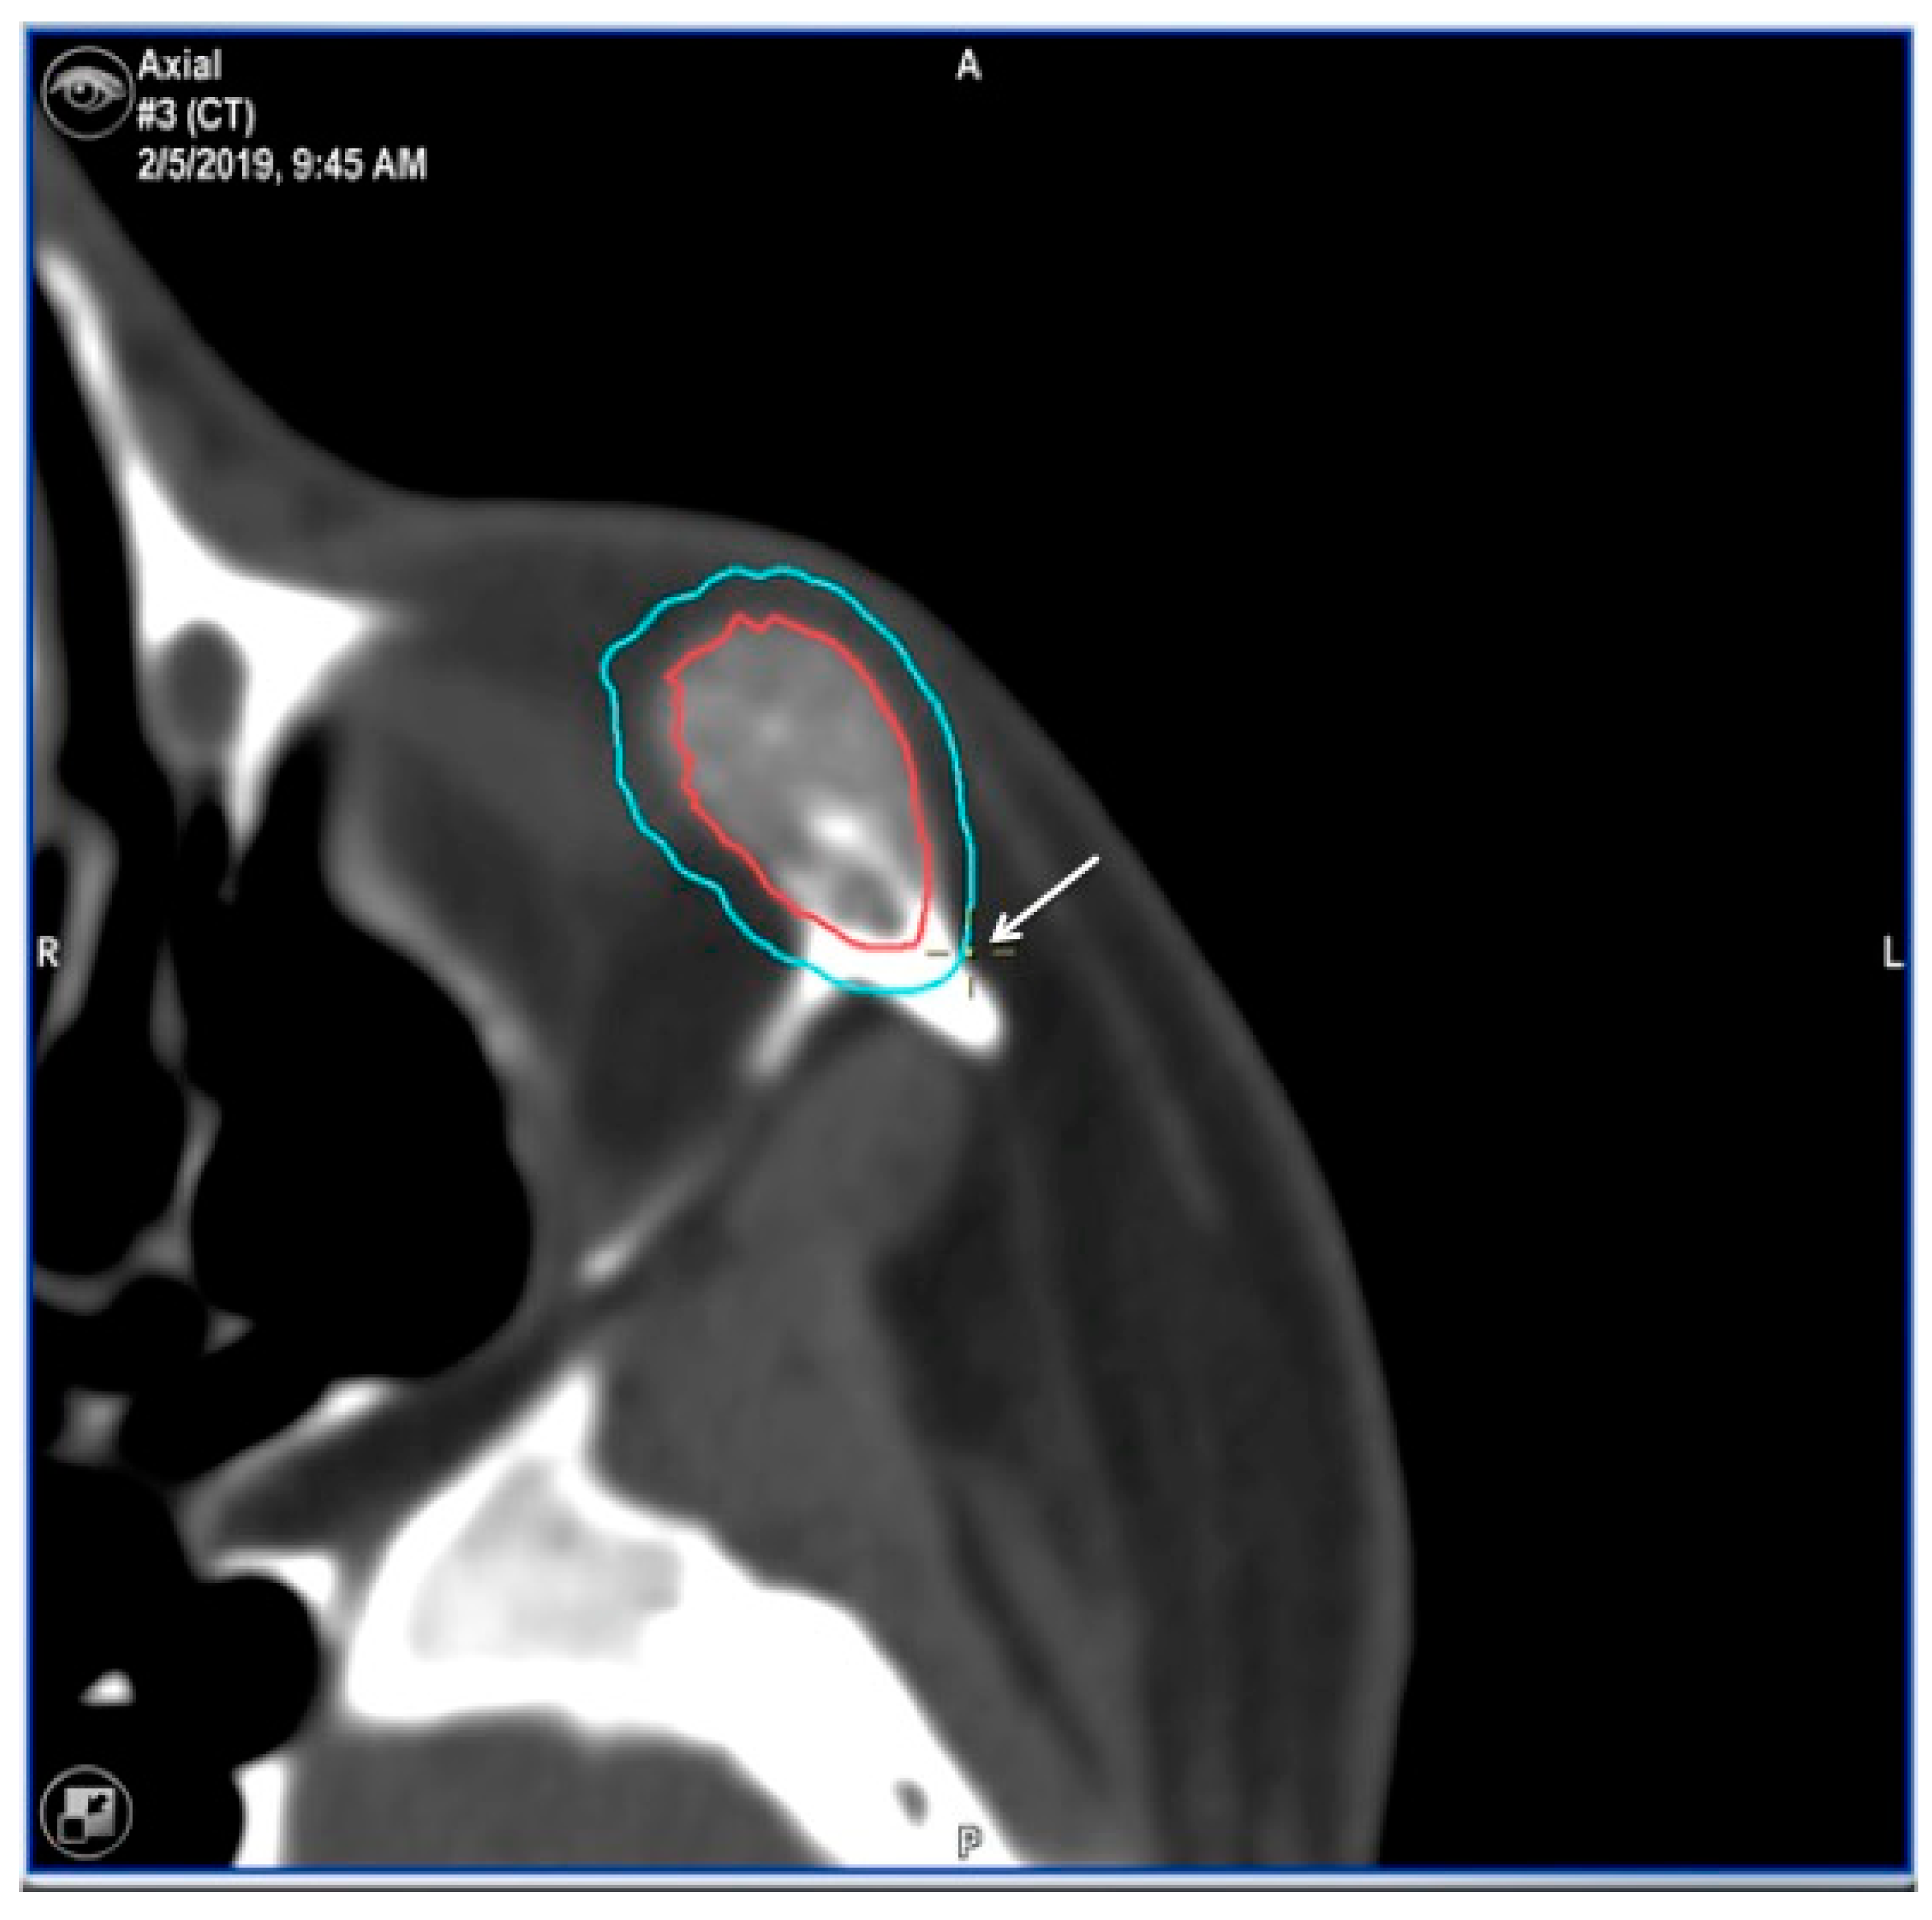

| 3 | 36/F | L/19 mm | Y | 6 mo | N | N | CT, MRI | Zygoma | Arteriovenous malformation | - | Resection + reconstruction | Y | Y | 1st, 2nd, 3rd | Transconjunctival + blepharoplasty + maxillary vestibular | Y | Piezoelectric device | N | PEEK prosthesis | 5 y/N |

| 4 | 47/M | L/30 mm | N | 2 y | N | N | CT | Zygoma | Intraosseous venous malformation | - | Resection + reconstruction | Y | Y | 1st, 2nd, 3rd | Transconjunctival + lateral canthotomy + maxillary vestibular | Y | Piezoelectric device | N | PEEK prosthesis | 6 y/N |